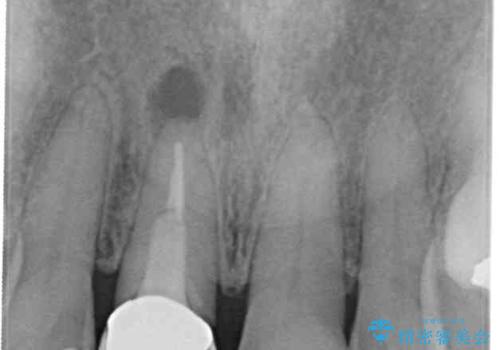

- 口腔内にある銀歯を全て外したいとのことで来院された患者様です。

土台に含まれている金属も含め、口腔内の金属は全て除去し、抜歯しなければならない歯は抜歯し、オールセラミッククラウンやセラミックインレーにて治療することとしました。

- 根管治療により痛みや腫れがひかない事や、術後に痛みや腫れが生じる事、治療によるファイル破折やパーフォレーションなどの偶発症、術後の歯根破折を生じる可能性もあります